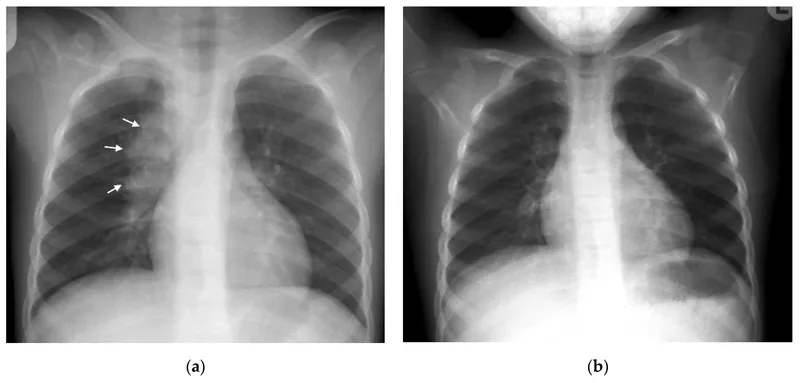

- Miliary (Disseminated): High fever, hepatosplenomegaly, respiratory distress. CXR: "millet seed".

- CXR: Hilar lymphadenopathy (commonest), Ghon complex, consolidation, miliary.